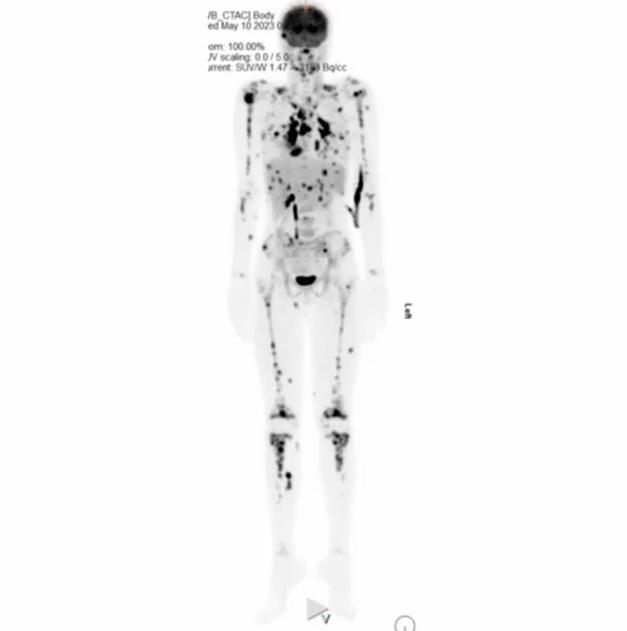

La pédiatrie est un domaine fascinant. Outre la grande résilience des enfants, nous sommes témoins de cas parfois complexes et impressionnants. Les cancers pédiatriques diffèrent de plusieurs manières de ceux des adultes. Par exemple, les enfants sont plus fréquemment atteints de sarcomes plutôt que de carcinomes. Une grande proportion des cancers chez l’enfant est d’origine hématopoïétique. Toutefois, du point de vue

diagnostique, près de la moitié des enfants atteints de cancer vont d’abord consulter un omnipraticien, puisque leurs symptômes sont souvent peu spécifiques. Cela risque malheureusement de retarder le diagnostic du cancer pédiatrique qui est plus souvent agressif et infiltrant. Dans le présent article, je vous présente un cas clinique que nous avons observé à l’Hôpital Sainte-Justine, au département de la médecine nucléaire.

Ksenia Sirotkina t.i.m. CHU Sainte-JustineCas clinique

Une jeune fille de 11 ans se présente à l’hôpital avec des maux de gorge et une altération de l’état général. Elle reçoit le diagnostic d’EBV positif (mononucléose infectieuse due au virus Epstein-Barr, herpès virus humain de type 4) avec un congé à la maison.

Or, l’état général de la patiente continue de se détériorer.

Elle est réadmise à l’hôpital avec une pancytopénie (baisse du taux des différentes cellules sanguines dans le sang), de la fièvre en alternance et une pneumonie ou atélectasie. Elle présente des signes d’activation macrophagique au bilan, et son test PCR pour EBV est négatif.

Ensuite, la patiente passe un scan thoraco-abdomino-pelvien sur lequel on constate une polyadénopathie thoracique ainsi que des lésions focales hépatiques et rénales.

Le radiologue suggère un TEP-CT et une éventuelle biopsie.

Cette dernière se présente au TEP-CT. Nous lui avons injecté une dose de 4,11mCi de F18-FDG et n’avons utilisé aucun agent de contraste pour la mise en image.

Sur les images du TEP-CT (figure 1), on peut constater plusieurs adénomégalies hypermétaboliques. Sachant qu’un ganglion normal mesure environ 1 mm, sur les images de la patiente, on trouve un ganglion situé latéralement à la trachée mesurant 18,0 mm avec un SUV max de 13,3. On constate aussi plusieurs foyers hypermétaboliques au niveau du tissu mammaire de façon bilatérale, plusieurs nodules pulmonaires, dont un avec un SUV max de 9,1, une atteinte rénale ainsi qu’une hépatomégalie avec au moins cinq foyers hypercaptants. De plus, il y a pré sence d’un

infiltrat pulmonaire très hypermétabolique avec un SUV max à 15,6. On trouve également plusieurs foyers hypercaptants osseux, dont un à la tête humérale droite avec un SUV max à 12,2, des foyers intramusculaires et même une suspicion d’atteinte du muscle orbitaire latéral droit. Il y a présence de foyers cutanés hypercaptants à la région fessière ainsi qu’aux cuisses, mais ces derniers sont plus discrets. Selon notre nucléiste, « Le tout laisse suspecter une atteinte néoplasique leucémique ou lymphomateuse sous-jacente ».